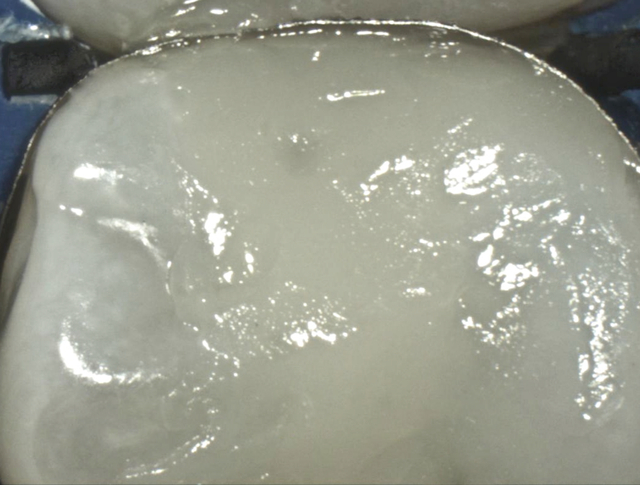

Mit Composit aufgefüllte Kavität (Intraoralkamera)

Entfernte Metallmatrize (Intraoralkamera)